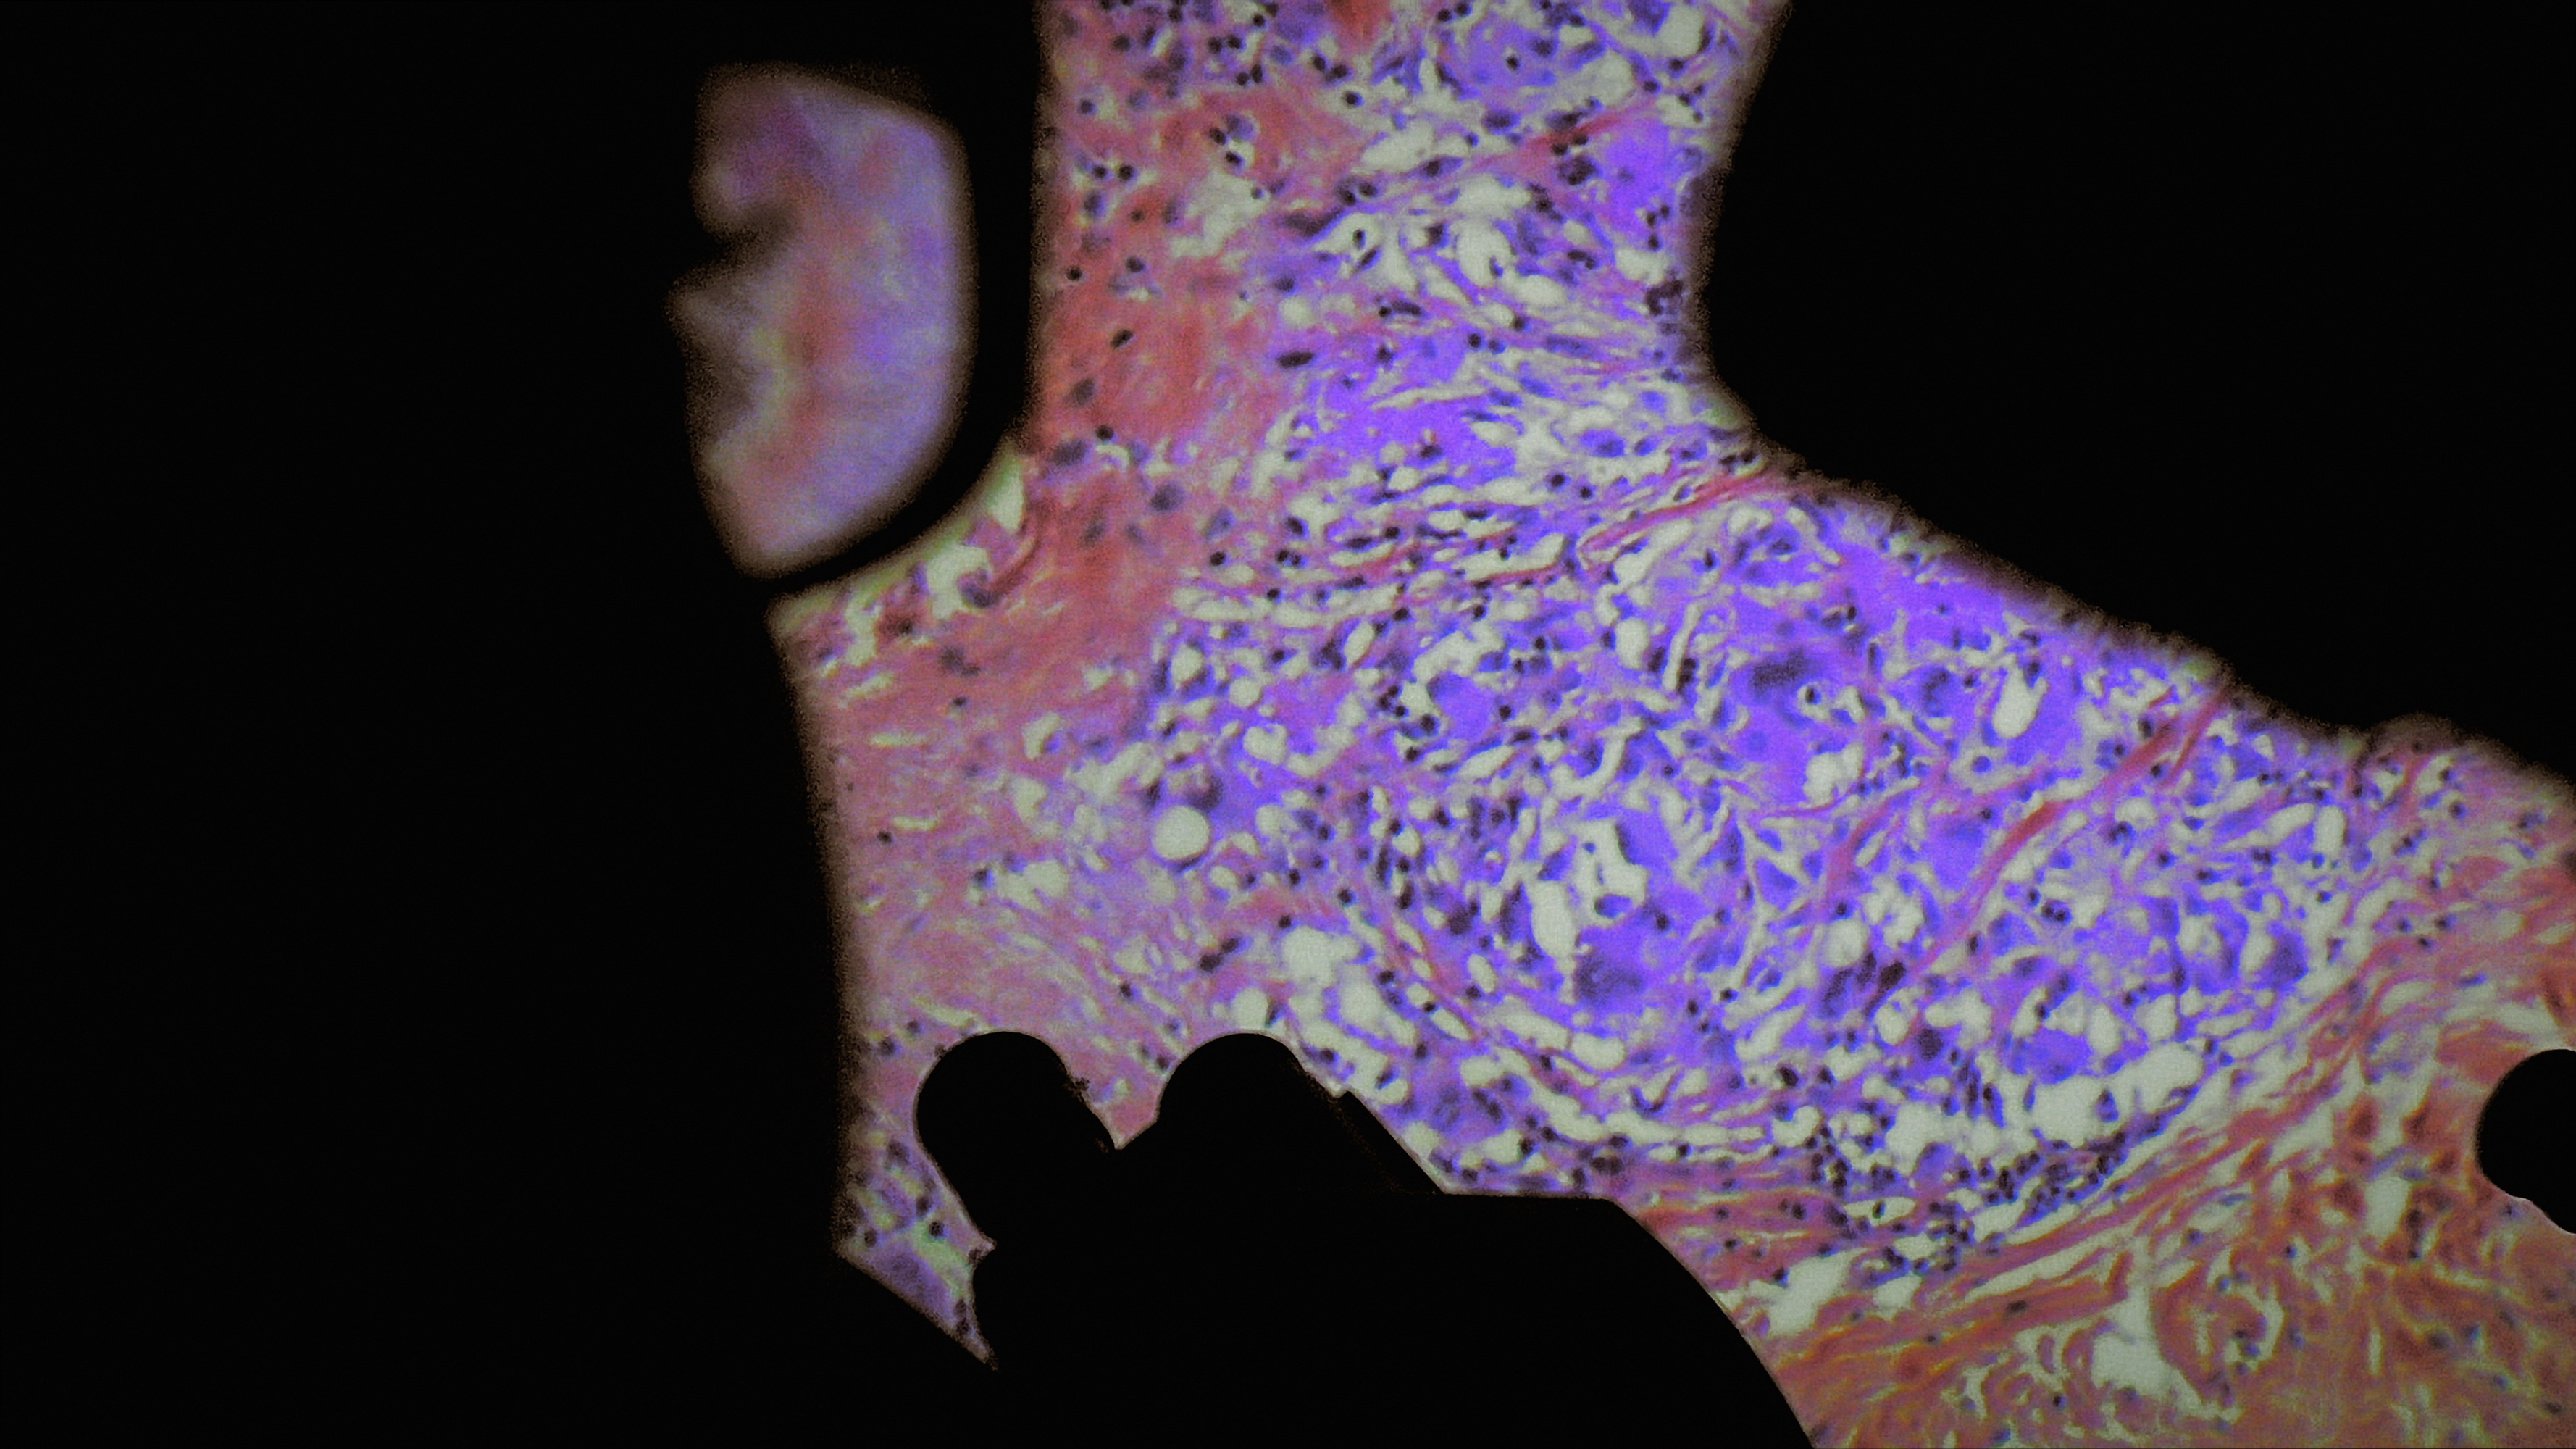

De Humani Corporis Fabrica

Verena Paravel & Lucien Castaing-Taylor

Norte Production

Quinzaine des Réalisateurs, Cannes 2022